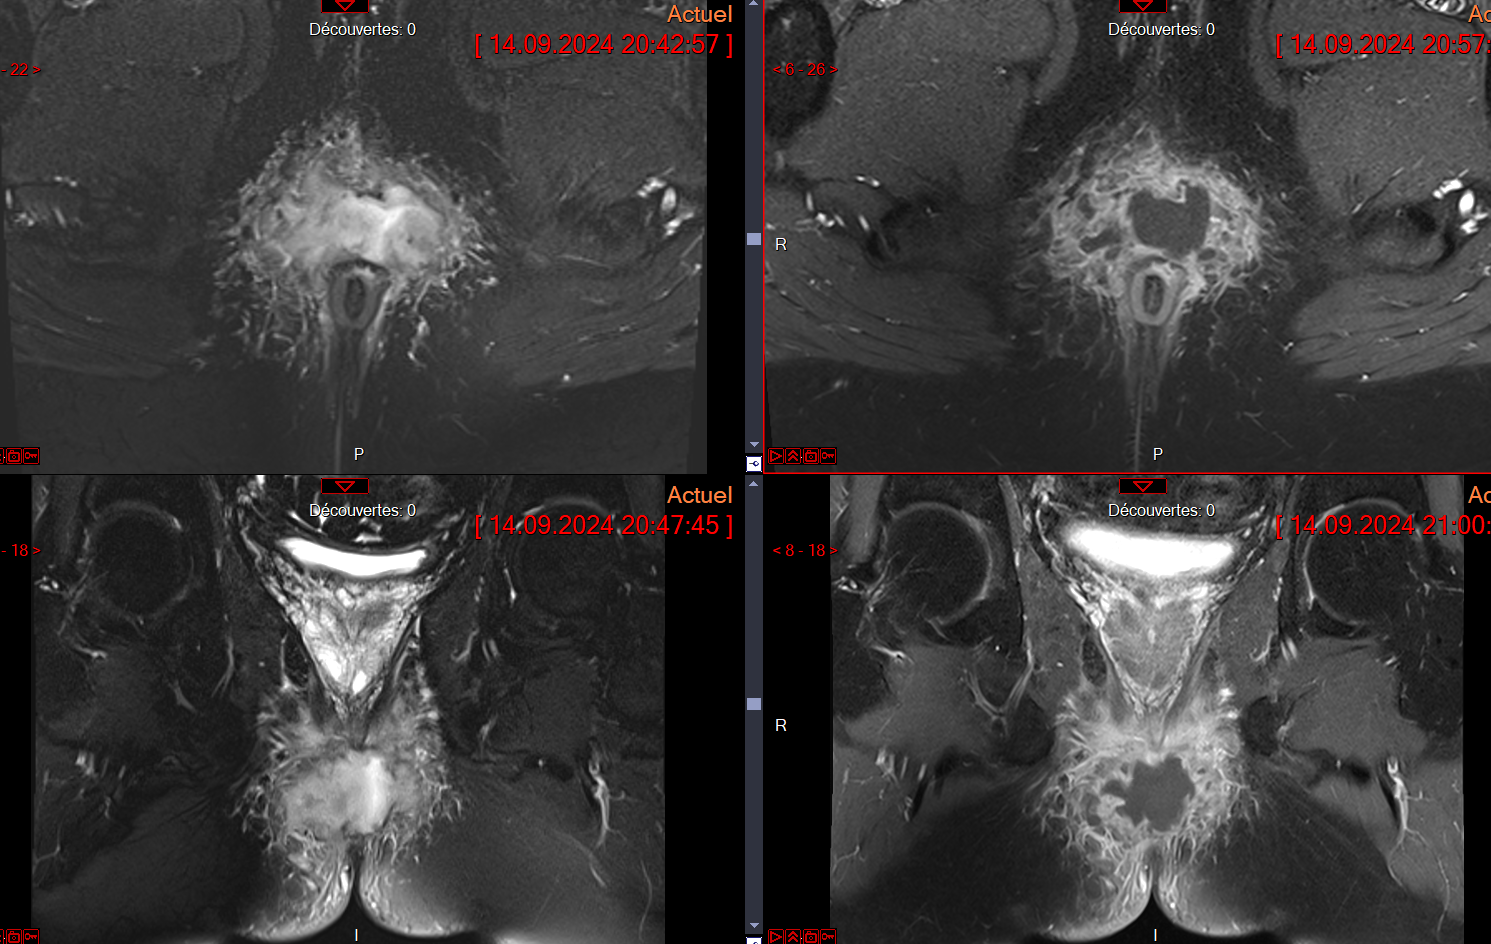

Abcès perianal

Abcès perianal

Abces intersphincterien avec phlegmo local

Abces intersphincterien avec phlegmo local